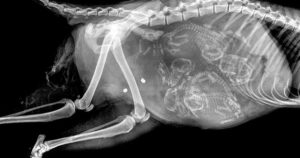

На рентгене хорошо просматриваются кости и позвоночник. Шерсть уже полностью сформирована. В целом на 50-й день котята уже готовы к рождению, но данный момент также зависит от породы.